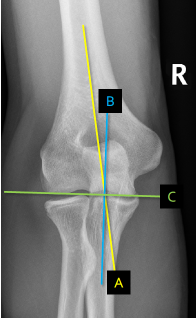

Q what is the name of these lines?

A:

Humeral shaft line : A line drawn through and parallel to the humeral shaft. The yellow line

Ulnar shaft line: A line drawn through and parallel to the ulnar shaft. Blue line

Humeral articular line: A transverse line drawn through the most distal surfaces of the trochlea and capitulum. Humeral Articular line

Q what is the name of this measurement? and what is the average + range?

A: Carrying angle (CA)

assesses the angle between the humeral and ulnar shaft lines. The average is 169°, with a range of 154-178°.

A: Humeral angle (HA) [Elbow]

assesses the angle formed by the humeral shaft and articular lines. The average is 85°, with a range of 72-95°.

A: Ulnar angle (UA)

assesses the angle formed by the ulnar shaft and humeral articular lines. The average is 84°, with a range of 72-99°.